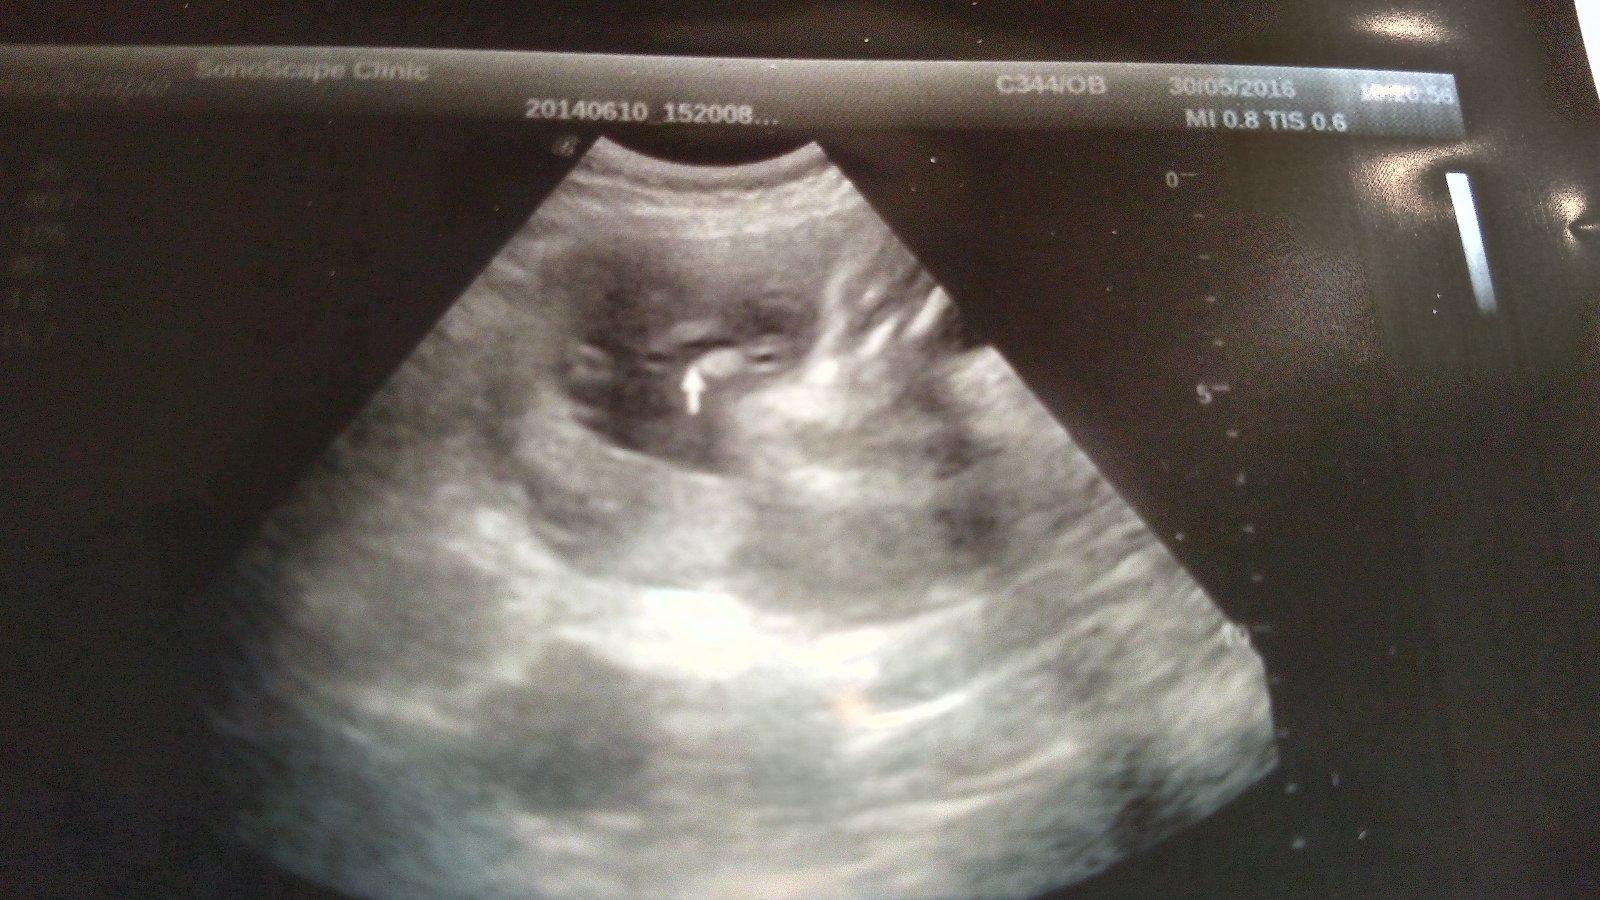

@estrellita uz jsem je tu vkladala prvni foto pred 2 lety jasny kluk..druhe fito nynejsi tehotenstvi ze 16tt a treti foto z 24tt.

Dole je zadek asi a nohy ma smerem doprava, ma je za hlavou..